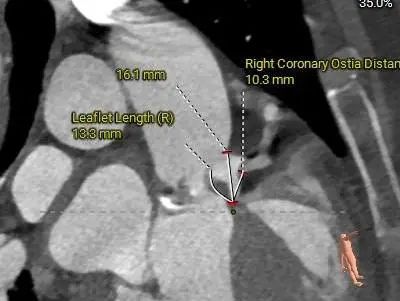

主动脉根部详细情况:

瓣上层面分析:

冠脉风险:

Left Coronary

LCA & Leaflet

三叶式主动脉瓣,瓣叶轻中度钙化并明显增厚,人工瓣膜锚定力尚可,左室流出道呈敞口型,综合多平面分析,预估瓣膜释放后有向下位移风险及瓣周漏可能。

左右冠开口高度稍低,综合瓦氏窦及窦管交界内径综合判断,预估左右侧冠脉阻挡风险适中,术中可根据球扩结果进一步判断,必要时行冠脉保护。